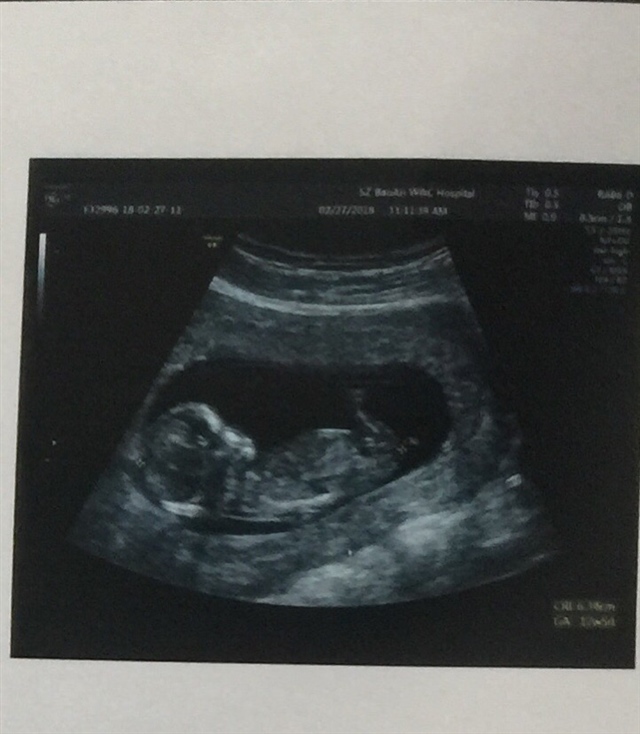

孕13周+4天

你做nt的时候有做早糖吗

Lirong[帖主]:NT不就是早糖吗?测颈部那个透明层是不是在正常范围内?接下来我要去做第二次产检